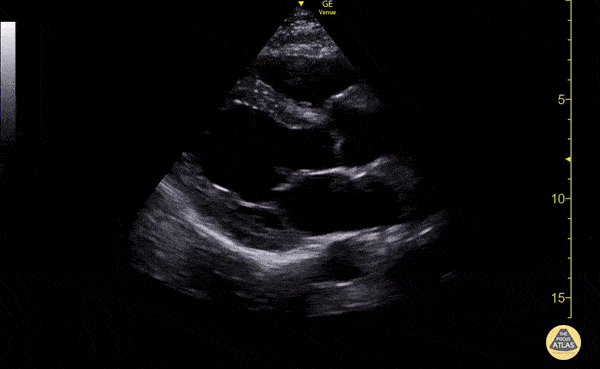

Normal Cardiac Anatomy - Normal Parasternal Long Axis (PLAX) View

Parasternal long axis view with normal ejection fraction Nigist Taddese MBChB. Division of Hospital Medicine, John H Stroger Hospital of Cook County